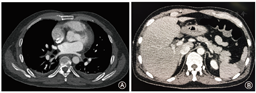

病例1患者男性,73岁。1个月前于我院行房颤导管消融术,主因"发作性胸痛伴寒战6 h"入院。患者6 h前于散步时突发胸骨后疼痛,为刺痛,吸气时加重,无放射痛,伴寒战、发热,体温最高37.5 ℃。既往有高脂血症病史10年,糖尿病史半年,陈旧性脑梗死半年。患者入院心电图示房颤心律,无明显ST-T改变,心肌损伤标志物未见明显异常,血常规示:白细胞计数(15.05×109 /L)及中性粒细胞(0.958)明显升高,D-二聚体2.102 mg/L。入院1.5 h后患者突发头晕、意识模糊,血压下降至75/50 mmHg(1 mmHg=0.133 kPa ),心电图示:Ⅲ度房室传导阻滞,下壁导联ST段弓背向上抬高,考虑"急性心肌梗死",予补液、多巴胺静脉泵入维持血流动力学稳定,以及阿司匹林、氯吡格雷负荷剂量后同时急诊行冠状动脉造影,但造影结果提示冠状动脉血管通畅,未见明显狭窄、痉挛及夹层等表现。入院第2天患者出现寒战、高热,体温升至39 ℃,伴呕吐咖啡色胃内容物300 ml,20 min后突发意识丧失。查体:血压90/60 mmHg,心率110次/min,中度昏迷,双侧瞳孔等大等圆,对光反射减弱。行头颅核磁共振成像检查显示:双侧大脑半球多发急性脑梗死。急查左心房肺静脉CT血管造影(computed tomography angiography,CTA ),结果显示:纵隔多发气体影,左心房后壁与左肺静脉交界处可见龛影(图1)。结合患者既往有房颤射频消融术病史,考虑"LAEF"可能,遂请心外科急诊行开胸探查并修补术,术中直视下可见左心房后壁5 cm×1 cm裂口,食管中段直径1.5 cm瘘管,术中行局部修补。手术过程顺利,术后继续予以生命支持及抗感染治疗,但患者仍持续处于深度昏迷状态,术后第5天由于感染中毒性休克及多脏器功能衰竭患者死亡。

病例2患者男性,52岁。1个月前于我院行房颤导管消融术,主因"寒战、高热2 d,突发胸痛4 h"入院。患者2 d前无明显诱因出现寒战,高热,体温最高40 ℃,自行口服退热药后缓解,4 h前患者突发胸骨后及心前区压榨性疼痛,范围手掌大小,伴四肢麻木、大汗,持续30 min无缓解,遂于当地医院急诊就诊,心电图示Ⅱ、Ⅲ、aVF、V2~V6导联ST段抬高0.5~1.3 mV。实验室检查:肌钙蛋白0.077 µg/L,白细胞计数(13.52×109/L)及中性粒细胞(0.930)升高,高敏C反应蛋白100.27 mg/L,考虑"急性心肌梗死",然而急诊行冠状动脉造影未见异常,术后复查心电图未见明显异常。术后6 h患者再发寒战、高热,体温39.1 ℃,予甲泼尼龙抗炎、莫西沙星抗感染治疗后体温恢复正常,术后18 h患者出现胸闷、心悸,伴大汗,伴意识淡漠,血压80/60 mmHg;心电图示:心房扑动,Ⅱ、Ⅲ、aVF及V2~V6导联ST段抬高。当晚通过网上求助联系我院主管医生,嘱继续禁食水、抗感染治疗,维持血流动力学稳定,同时迅速转往我院。次日凌晨4点半患者转入我院后紧急完善左心房CTA及头颅核磁共振成像检查,弥散加权成像(diffusion weighted imaging,DWI )序列示胼胝体体部、双侧小脑、双侧额颞顶枕叶多发片状新鲜脑梗死(图2)。左心房CTA示纵隔内仅见单个可疑气体影,但脾脏出现新发梗死灶(图3)。经多学科会诊后,考虑"左心房食管瘘"可能性大,急诊行开胸探查术,术中可见左房后壁近左肺静脉处2.0 cm×1.5 cm裂口,以牛心包补片修补裂口后继续探查,发现食管在左下肺静脉上缘附近与心包致密粘连。分离食管和心包后见食管壁及黏膜缺口长约3 cm,缝合黏膜及食管肌层。术后予呼吸机辅助通气治疗,16 h后恢复意识,术后第2天拔除气管插管。患者血培养示:以革兰氏阳性菌为主的混合感染,予亚胺培南联合左奥硝唑抗感染后未再出现寒战、发热。术后第10天复查食管造影,口服造影剂后见食管中下段局部管壁不规则,管壁尚柔软,管腔通畅,未见造影剂外漏。遂逐步恢复患者自主进食。术后第26天患者康复出院,未遗留神经系统症状。